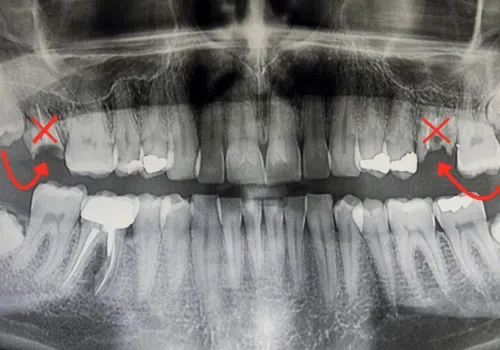

Das ALL-ON-4® Verfahren (auch bekannt als Pro Arch oder „Tooth in 1 Hour“ / „feste Zähne in einer Stunde“) wenden wir bei Patienten an, die in einem oder beiden Kiefern zahnlos sind oder nur noch wenige stark beschädigte Zähne haben. Diese Patienten leiden oft unter dem Einfluss von unschönen Prothesen auf ihr Aussehen oder können nicht alles essen, was sie möchten, da schlecht sitzender Zahnersatz oder lockere Zähne dies verhindern.

Dank einer speziellen Einsetz-Technik der Implantate und einer 3-dimensionalen computergestützten Planung ist dies auch bei Patienten mit stärkerem Knochenabbau (z.B. durch jahrelanges Tragen einer Totalprothese oder nach einem Unfall) möglich, die sonst aufwendige Knochenaufbauten benötigen würden.